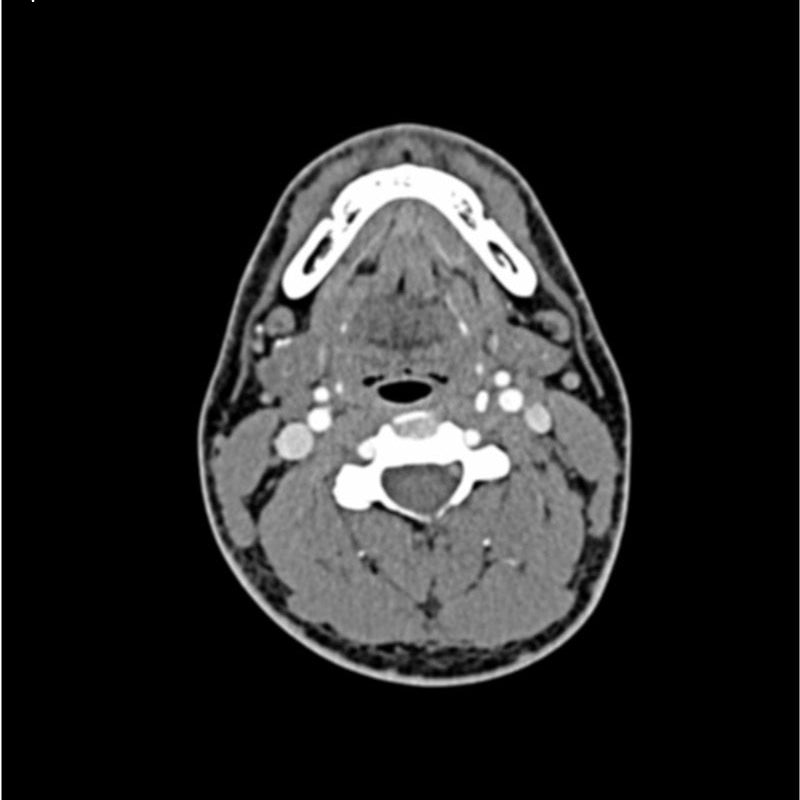

This phantom simulates a contrast medium enhanced head in arterial phase (CT angiography). It covers the vertex to the fifth cervical vertebra. The phantom has 10 low-contrast lesions in the centrum semiovale and the right hemisphere has an arteriovenous malformation.

The phantom can be used in CT (including CBCT) to evaluate and optimize imaging performance and AI-enabled diagnosis. It is also suited for training purposes. The phantom provides a detailed and realistic simulation of vascular structures, soft and bone tissue. Air voids are filled with a cellulose-polymer composite of approx. -160 HU.